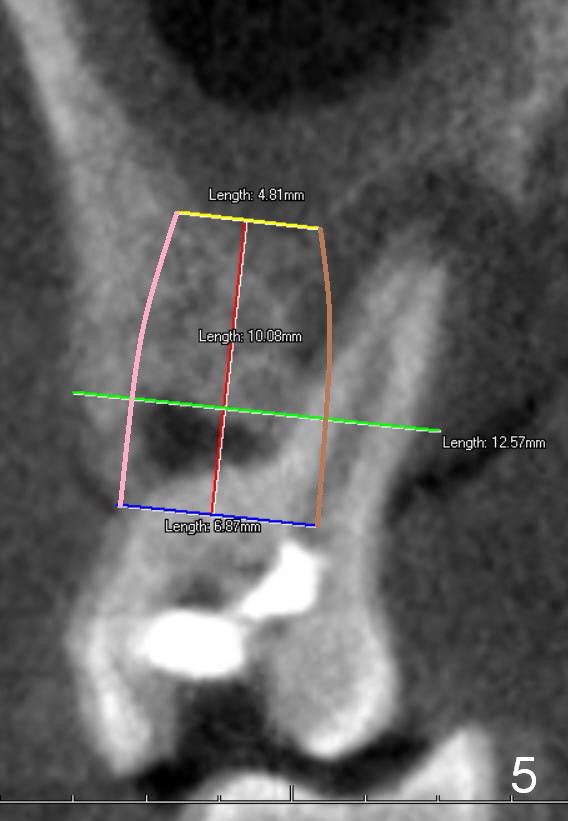

Two years post RCT, there is radiolucency around the MB root of the tooth #3 (Fig.1,2). Eleven days later, there is acute infection associated with MB and DB root fracture (Fig.3). According to the X-ray taken 11 days earlier (Fig.1,4), a long tissue-level implant (6x17 mm) is suitable for the site. In accordance with CBCT (coronal (Fig.5) and sagittal (Fig.6) sections) taken prior to RCT, a short bone-level implant (6.9x10 mm) is a more reasonable choice.

After extraction, the socket will be studied to determine where the bone is and where bony defects are for the site of the initial osteotomy. Start with 2 mm pilot drill or RT2, apparently ~ 6 mm depth, followed by reamers 2.5-3.5 mm and Tatum taps 4.5-7x17 mm (14 mm depth from gingival margin). Use a latch adapt with the torque wrench. Due to severe bone loss, the tap should not be too large (6 mm). If insertion torque is high and bone morphology is favorable, change to DIO taps and take necessary PAs to decide the length of the implant relative to the sinus floor and trajectory. If the depth is 10 mm or less, use SM; 12 mm UF. Based upon the most recent X-ray (Fig.3 with large lesion), the implant should be large and long (Fig.7: 7x17 mm).